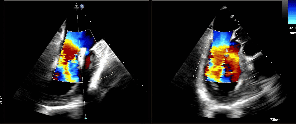

TEE

TEE-2D血流

TEE-3D血流